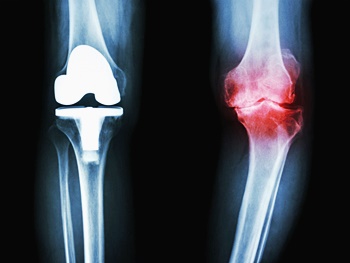

관절염 증상이 호전이 없고 변화가 진행되어 일상생활에 심한 지장을 줄 경우 시행됩니다. 관절경을 이용하여 관절 내부를 세척하고 유리체와 활액막 등을 제거하여 증상을 완화시키는데요. 통증이 적고 회복 기간이 빠른 장점이 있지만 완전한 치료가 되지는 않습니다.

절골술은 관절의 한 부분만 증상이 발생한 경우 관절 정렬을 바꾸어 주는 것을 말합니다. 이외에도 소파 관절 성형술, 다발성 천공술, 관절 성형술, 관절 고정술로 나누며 관절염의 발생 부위나 특성에 따라 다양한 수술적 치료를 진행할 수 있습니다.